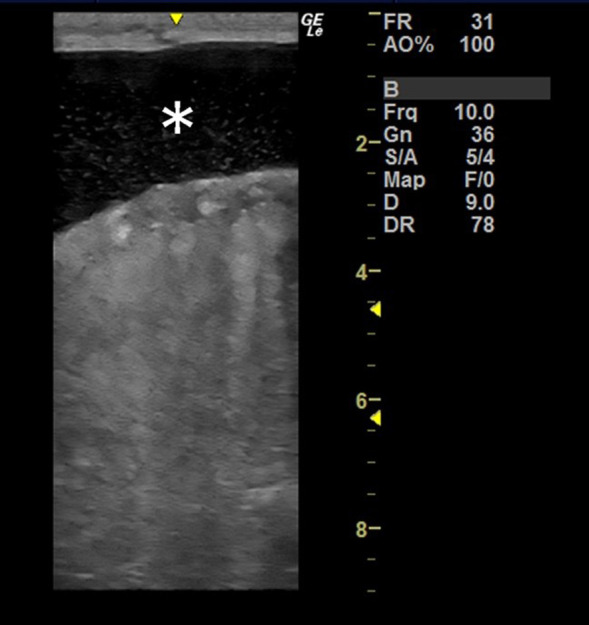

马睾丸动脉炎通常是线虫幼虫迁移或马动脉炎病毒(EAV)感染的结果。然而,也有报道称睾丸动脉炎没有这些感染的证据,其潜在的发病机制仍不清楚。我们在一匹阴囊肿大的 3 岁雄性重型草马身上发现了没有线虫或 EAV 感染证据的睾丸动脉炎。从外观上看,由于水肿,睾丸静脉丛的体积明显增大。从组织学角度看,在精索、睾丸鞘膜丛(最严重)、睾丸和附睾弥漫性地观察到非化脓性坏死性睾丸动脉炎,其特征是淋巴细胞浸润和动脉壁纤维素性坏死。我们无法确定动脉炎的病因,如病毒感染或自身免疫异常。

Equine testicular arteritis commonly occurs as a consequence of the migration of nematode larvae or equine arteritis virus (EAV) infection. However, testicular arteritis without evidence of these infections has been reported, and the underlying pathogenesis remains unclear. We encountered testicular arteritis without evidence of nematode or EAV infection in a 3-year-old male heavy draft horse with scrotal enlargement. Grossly, the volume of the pampiniform plexus was markedly increased due to edema. Histologically, non-suppurative and necrotizing testicular arteritis, characterized by lymphocyte infiltration and fibrinoid necrosis of the arterial walls, was diffusely observed in the spermatic cord, pampiniform plexus (most severe), testis, and epididymis. We were unable to identify the cause of arteritis, such as a viral infection or autoimmune abnormality.